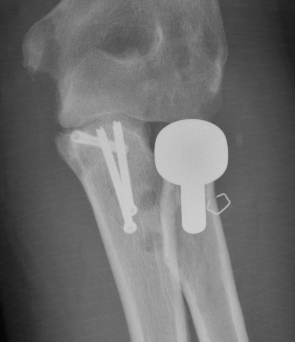

1. Restore coronoid stability - ORIF type II / III, suture repair type I

2. Restore radial head stability - radial head ORIF or arthroplasty

3. Restore lateral stability - LCL repair and common extensor origin +/- reconstruct +/- internal brace

4. +/- Restore medial stability - repair MCL if residual stability

5. +/- External fixation / internal joint fixation